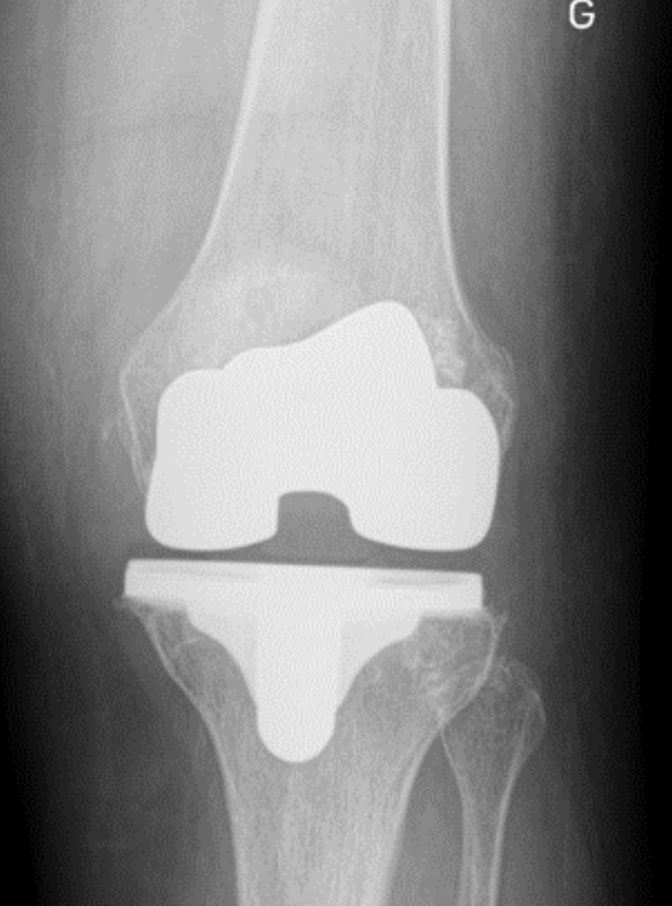

Une prothèse totale du genou consiste à retirer les zones usées du cartilage et des os du genou et à les remplacer par des pièces artificielles conçues pour restaurer la mobilité et soulager la douleur. Cette procédure peut être réalisée avec une technique mini-invasive pour une récupération plus rapide.

Une opération de prothèse du genou est généralement réalisée sous anesthésie générale ou rachi-anesthésie. Une incision est pratiquée au niveau de la partie antérieure du genou, et une partie de la rotule peut être déplacée pour accéder à l'articulation. Le cartilage usé est retiré, et les surfaces du fémur, du tibia et de la rotule sont préparées pour recevoir les composants de la prothèse. La prothèse totale du genou est composée de trois parties : la partie fémorale, la partie tibiale et la partie rotulienne. Une fois implantée, la prothèse est positionnée pour assurer une stabilité optimale du genou. La durée moyenne de l'opération est d'environ 1 heure et demie, et l'hospitalisation dure généralement environ 5 jours.